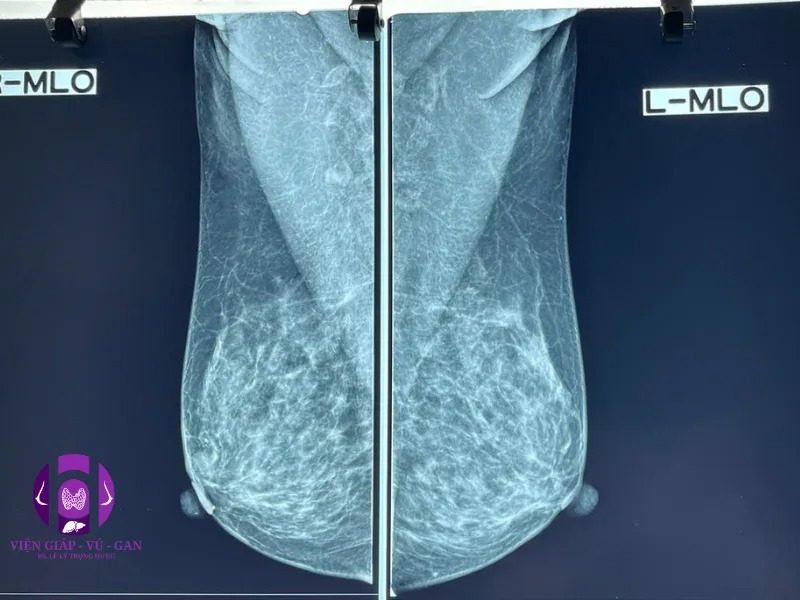

NHŨ ẢNH:

- Vú phải: sau núm vú, có khối đặc, đậm độ trung bình, bờ đa cung, không vi vôi, kt # 10x10x10mm.

- Hạch nách phải có vài khối viêm kt #10-15mm.

- Kết luận: Tổn thương vú phải ( BI-RADS 4A)